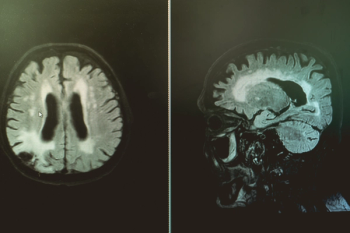

Greater imaging utilization has increased the prevalence of incidental findings or incidentalomas, but unclear clinical context and guidelines complicate management. Accordingly, these authors offer a thorough review of the literature and discuss new opportunities for improving interdisciplinary management strategies.